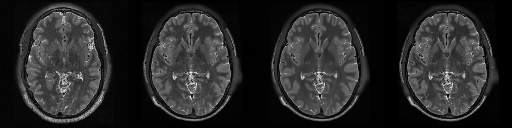

HCP T2w dataset

We utilize images from the publicly available Human Connectome Project (HCP) [51] T2-weighted (T2w) images dataset for the task of compressed sensing, which contains brain images from 47 patients. The HCP dataset includes cross-sectional images of the brain taken at different levels and angles.

Compressed sensing

We train a flow-based model from scratch on 10,000 randomly sampled images, utilizing the ncsnpp architecture [9] with minor adaptations for grayscale images. We employ compression rates , meaning . The measurement operator is given by a subsampled Fourier matrix, whose sign patterns are randomly selected. We evaluate our reconstruction algorithm’s performance on 200 randomly sampled test images.

We present the quantitative and qualitative results of compressed sensing in Tab. 1 and Fig. 4, respectively. As shown in Tab. 1, our method consistently achieves the best performance across varying compression rates . In Fig. 4, our method produces reconstructions that are more faithful to the original images, with fewer artifacts, leading to higher accuracy and clearer details.